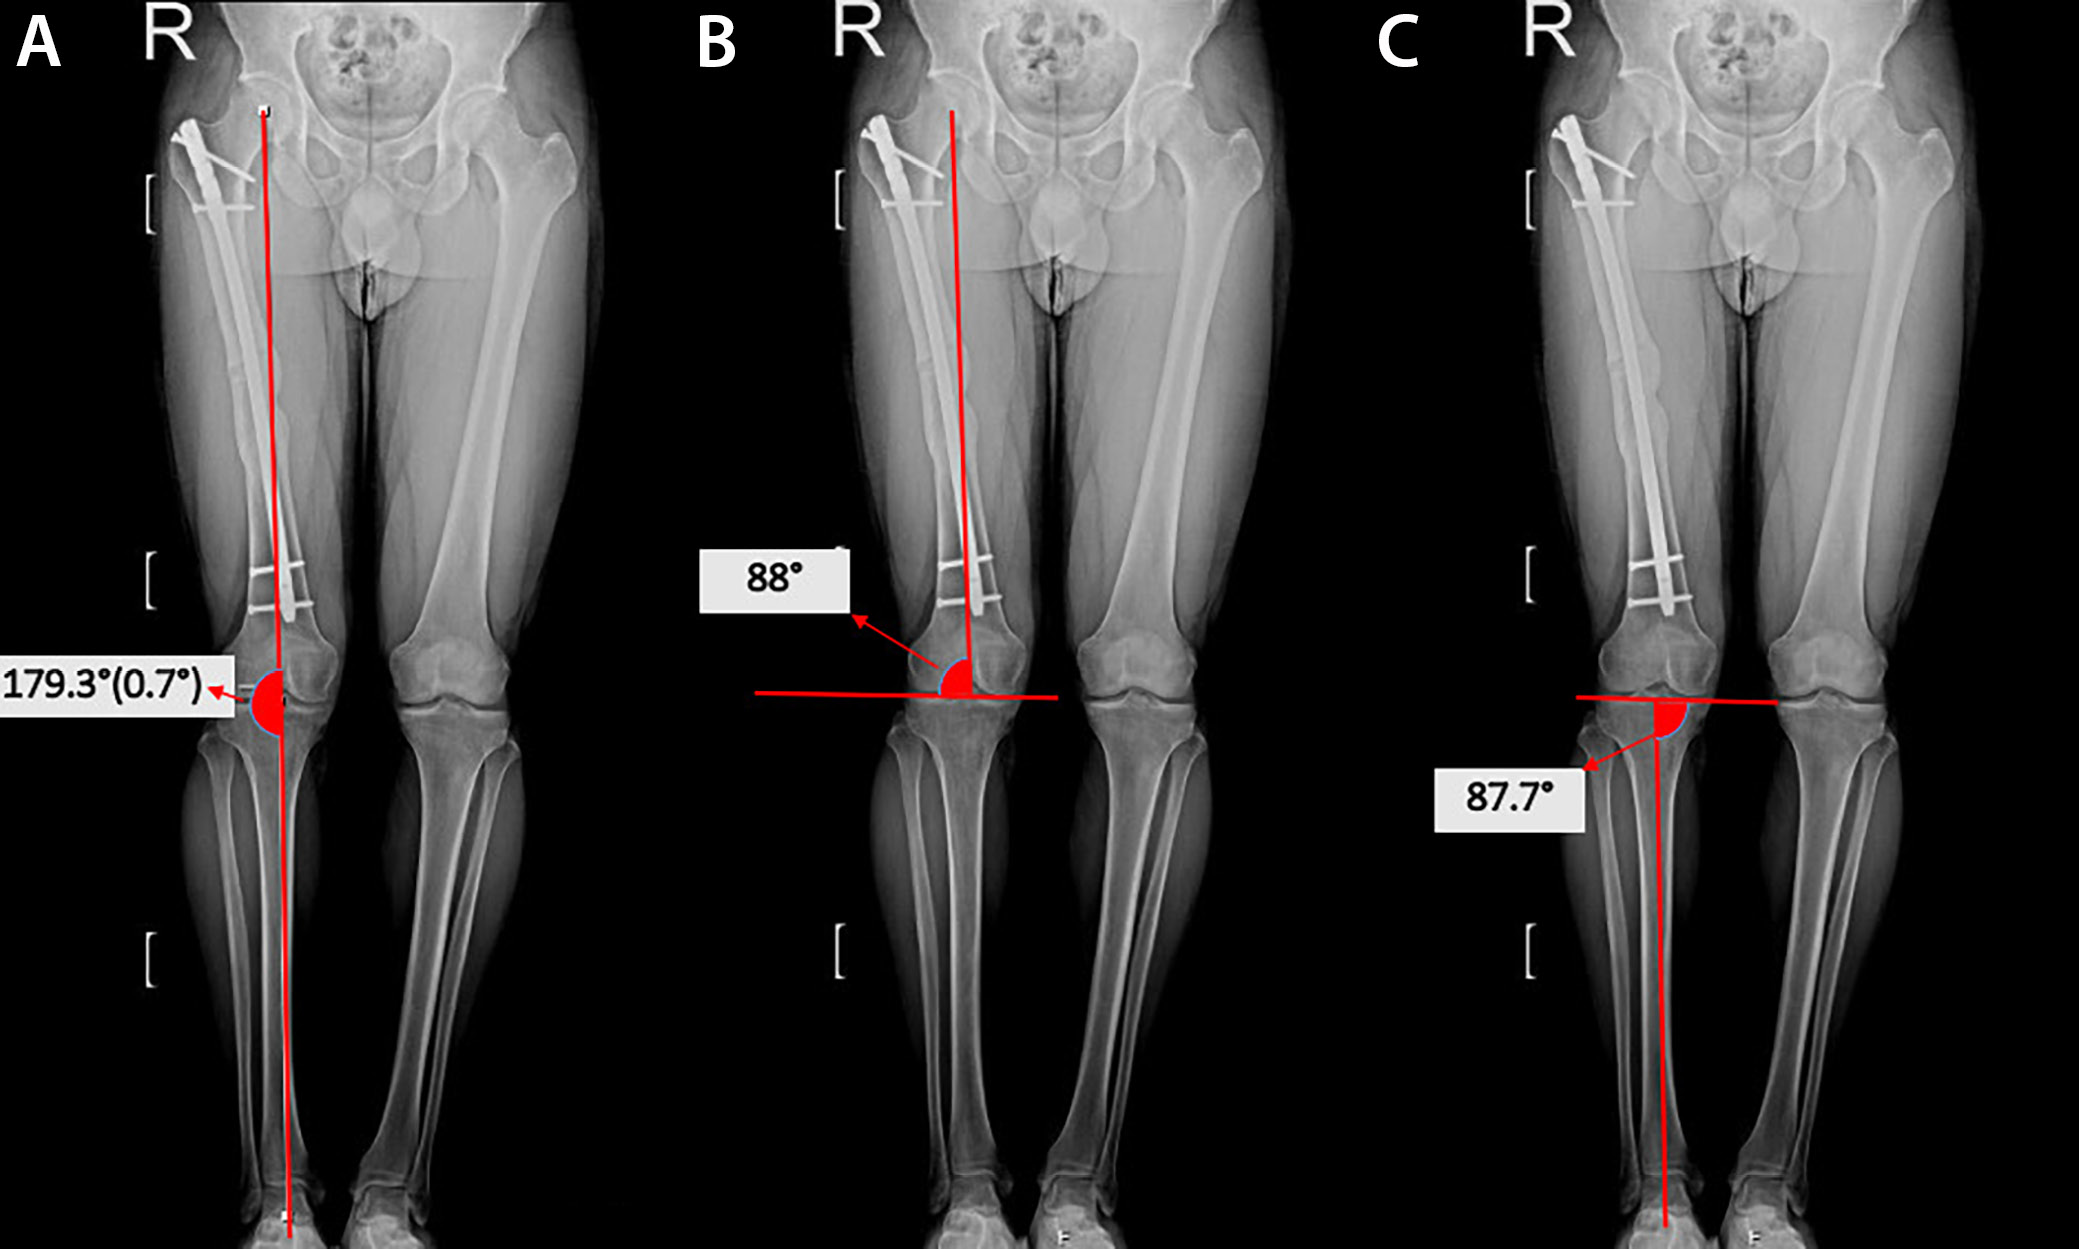

Orthoroentgenograms were used to assess femoral length discrepancies, coronal plane angulations (varus/valgus) at the fracture line, mechanical lateral distal femoral angle (mLDFA), mechanical medial proximal tibial angle (mMPTA), and postoperative lower extremity mechanical axis angle (MA), and to compare the sizes of the lesser trochanters on both sides to detect rotational deformity (Figure 1, Figure 2, Figure 3). Coronal plane deformity of the femur was evaluated by drawing one line from the fracture site to the proximal center of the medullary canal and another line from the fracture site to the midpoint of the distal femoral articular surface. The angle between these 2 lines was then measured (Figure 1C, Figure 2C).

The results of the radiological evaluations are shown in Table 3. There was no difference between the 2 groups in terms of mLDFA, mMPTA, and lower extremity MA angle measured at the last follow-up (t = 0.778, p = 0.415; t = 0.952, p = 0.350; and U = 1069, p = 0.627, respectively).